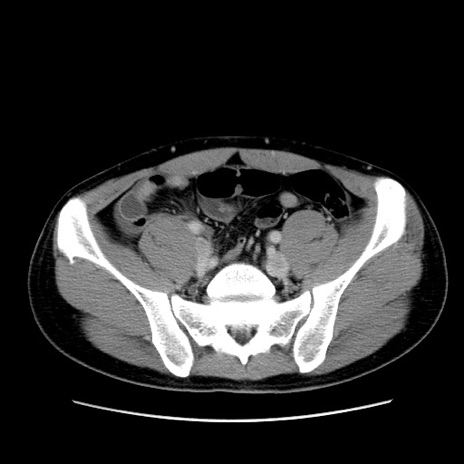

症例36(横断像)

【症例】20歳代 男性

【主訴】心窩部痛

【現病歴】今朝より上腹部痛あり。一旦軽快していたが再度出現したため救急要請。昨日夕に白身の魚を含む刺身を食べた。

【身体所見】BP 136/89mmHg、HR 74/min、BT 37.0℃、腹部:膨満、軟、心窩部に圧痛あり。反跳痛なし、筋性防御なし、腸雑音やや亢進あり。

【データ】WBC 17700、CRP 0.48

冠状断像